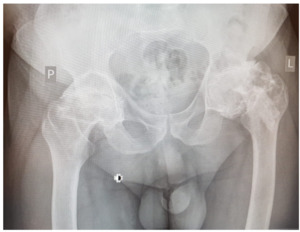

A 35-year-old man suffering from necrosis of the femoral head of the left hip joint underwent surgical treatment consisting of drilling the necrotic head and filling the femoral neck with bioceramic elements (Fig. 1). The porous bioceramic material had the following chemical composition: 97% Al2O3, 2.5% MgO, and 0.5% CaO.17 The manufactured material (open porosity, 70–80%) was characterised by external and internal pores with pore diameters between 100 and 800 μm. The outer and the inner pores were filled with healthy bone tissue adherent to the ceramic material. Bieniek17 the material was used to fill bone cysts and postsurgical or trauma-related bone defects.

Twenty-seven years later, due to the development of the secondary degenerative disease of the left hip joint, the patient underwent implantation of a total hip joint replacement in which metal/polyethene articulation was used, and ceramic fragments were carefully removed intraoperatively. In this case, a protocol of rinsing the operated joint with an electric pulsation system was used during the revision procedure, as in the case of PJI (periprosthetic infection). Six years after this procedure, the patient was observed to have deformation of the metal head of the endoprosthesis, appearing in control X-rays with relatively minor changes in the thickness of the polyethylene (acetabular insert). The head deformation was accompanied by defects that were visible in the form of radiolucencies located in the third, closer to the femur and in the area of the lower pole of the acetabulum (Fig. 2). The patient reported increasing pain in the left hip joint (increasing with weight bearing), and therefore qualified for revision surgery. The examination revealed severe macroscopic deformation of the metal head of the endoprosthesis, the formation of extensive defects in the proximal part of the femur (greater and lesser trochanter), with perforation of the femur and loosening of the stem of the primary endoprosthesis, as well as bone cysts in the periacetabular area (without destabilisation). The cavities were filled with dark content (specific to metal abrasion products), indicating severe metallosis and the metal neck of the femoral stem was severely scratched. Intense contamination of the polyethylene surface of the insert of an unknown origin was also observed (Fig. 3,4). The elements of the primary endoprosthesis removed during the procedure were subjected to further macroscopic and microscopic examination.